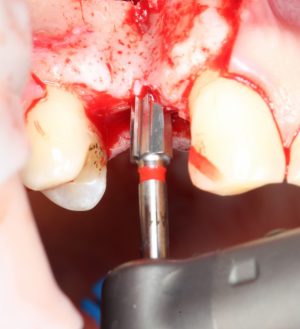

Подготовка лунок для имплантатов

Прежде, чем приступить к аугментации (пластике) лунок зубов, мы подготовили лунки для имплантатов. В таких клинических случаях нет необходимости в использовании шаблона. Вместо этого, мы применяем общепринятые правила позиционирования и соблюдаем рекомендации производителя по хирургическому протоколу:

В процессе ирригации лунки промываются, что позволило нам еще раз подтвердить ранее сделанные выводы. С помощью аналогов имплантатов, входящих в хирургический набор Xive, мы проверили возможность стабилизации имплантатов в будущих лунках. Исходя из правил подбора и позиционирования имплантатов (я очень рекомендую почитать об этом здесь>>) мы остановились на Xive S диаметром 3,4 мм и длиной 13 мм.

Подготовка двух лунок для имплантатов занимает около 10 минут.